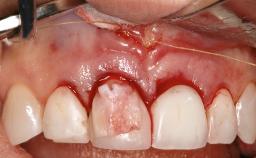

Surgical Management of Peri-Implantitis: Removal of Implant Due to Recurrent Infection Using an Implant-Retrieval Tool

Despite anti-infective surgical treatment, some patients may experience recurrent infection and progressive bone loss requiring additional treatment. This case describes a conservative approach using an implant retrieval tool without the need for excessive bone removal or use of a trephine.

A 65-year-old female patient was referred to the periodontist for assessment and management of infection associated with an implant at site 12. The general dentist had noted suppuration on probing during examination.